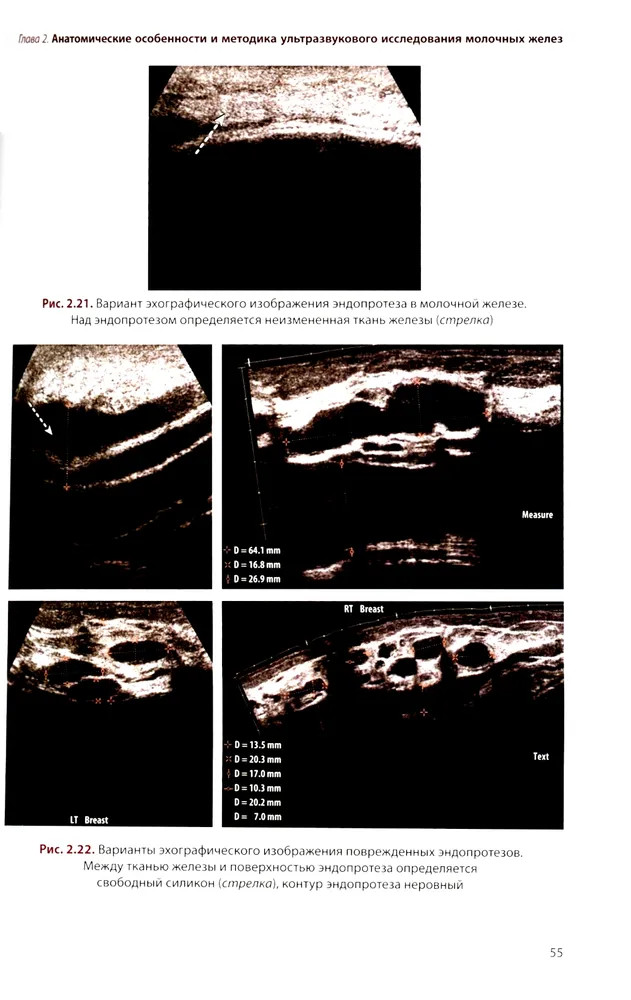

💳 Оплатить за товар можно при получении 🇰🇿 Есть бесплатная доставка по Казахстану от 1 дня 🎁 Копите бонусы с каждой покупки Руководство посвящено изучению возможностей различных методик УЗИ в диагностике доброкачественных и злокачественных опухолей молочных желез, доброкачественных процессов и воспалительных заболеваний. На основе анализа литературных данных рассматриваются вопросы этиологии, морфологии и классификации опухолей молочных желез. Отдельная глава посвящена методике и нормальной ультразвуковой анатомии молочных желез. Подробно изложены семиотика опухолей молочных желез, а также вопросы применения УЗИ в определении стадии опухолевого процесса согласно классификации TNM. Для специалистов по лучевой диагностике, а также врачей других специальностей в области маммологии. Руководство может быть рекомендовано для подготовки в системе последипломного непрерывного профессионального образования. |